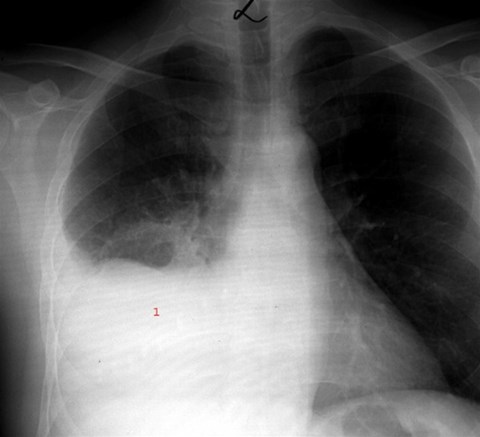

Lungebetaendelse symptomer born. Far du en forkolelse der ikke vil ga vaek eller oplever du symptomer som beskrevet ovenfor er det vigtigt at du soger laege. Symptomer pa lungebetaendelse hos born og spaedborn. Lungebetaendelse forekommer isaer om vinteren. Hos born kan sygdommen desuden forveksles med blindtarmsbetaendelse. Born med kroniske sygdomme er saerligt udsatte for lungebetaendelse pga. Kold lungebetaendelse rammer hovedsageligt born over 5 ar. En kold lungebetaendelse starter som en almindelig forkolelse med ondt i halsen hovedpine lobende og taet naese let temperatur forhojelse og tor hoste. Alle born undtagen spaedborn under 6 maneder far feber hvis de har lungebetaendelse. Er du i tvivl om dit barn er meget sygt og eventuelt har lungebetaendelse kan man stille sig selv disse sporgsmal. Hoj alder darlig ernaering fejlsynkning og anden akut eller kronisk sygdom fx hiv samt behandling med kemoterapi eller immunterapi oger risikoen for lungebetaendelse. Du skal ringe til laegen med det samme hvis barnet far. Er det helt anderledes end det plejer at vaere. Oget risiko for lungebetaendelse. Lungebetaendelse hos helt sma born. Born og spaedborn oplever typisk kun folgende symptomer.